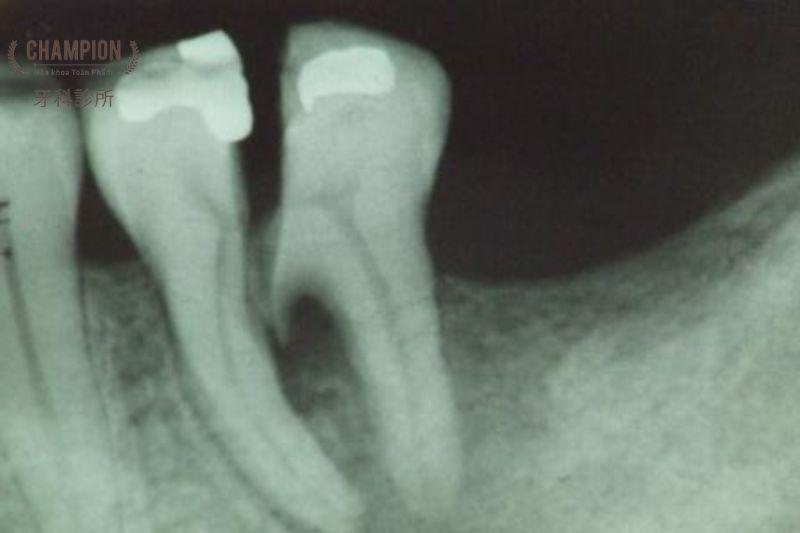

Bên cạnh khám lâm sàng, chụp X-quang là phương pháp vô cùng hữu ích để phát hiện những vết nứt không thể nhìn thấy bằng mắt thường. Dựa vào hình ảnh X-quang, các bác sĩ nha khoa có thể xác định chính xác vị trí, mức độ và hướng lan của các vết nứt trong răng, từ đó lên kế hoạch điều trị phù hợp.

Bắt đầu bằng khám lâm sàng kỹ càng để phát hiện các dấu hiệu nứt răng, các bác sĩ sẽ tiến hành chụp X-quang và chụp CT Cone Beam hiện đại. Với độ phân giải cao, các kỹ thuật này cho phép quan sát chi tiết cấu trúc răng, tủy, nướu và xương hàm, từ đó đưa ra chẩn đoán chính xác nhất về tình trạng nứt răng của bệnh nhân.